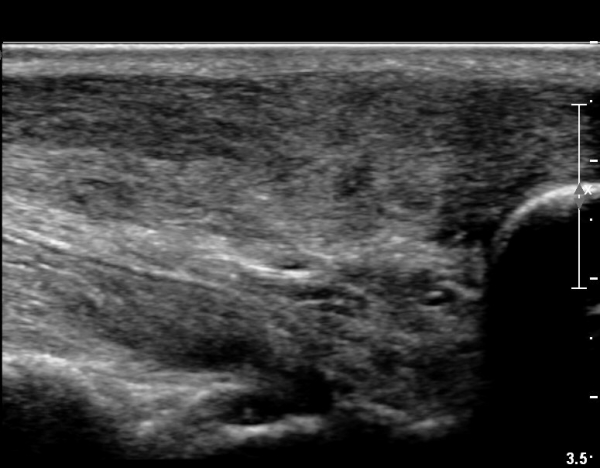

¾ÆÅ³·¹½º°Ç Á¾´Ü¸é°Ë»ç¿¡¼­ ¾ÆÅ³·¹½º°Ç ¸»´ÜºÎ¿¡ ¾ÆÅ³·¹½º°ÇÀÇ Àú¿¡ÄÚºÎÁ¾, ±¹¼ÒÀû ¿¬°á¼º ¼Ò½Ç,

¹ß¸ñ°üÀý ÈĹæºÎ¿¡ ¼ö¾×Àú·ù°¡ °üÂûµÊ(»çÁø 3, 4, 5).

¾ÆÅ³·¹½º°Ç ±ÙÀ§ºÎ Á¾´Ü¸é°Ë»ç¿¡¼­ ¾ÆÅ³·¹½º°ÇÀÇ Àú¿¡ÄÚºÎÁ¾, ±¹¼ÒÀû ¿¬°á¼º ¼Ò½ÇÀÌ °üÂûµÇ¾î

ÆÄ¿­ÀÌ ±¤¹üÀ§ ÇÑ °ÍÀ» º¸¿©ÁÜ(»çÁø 6, 7).